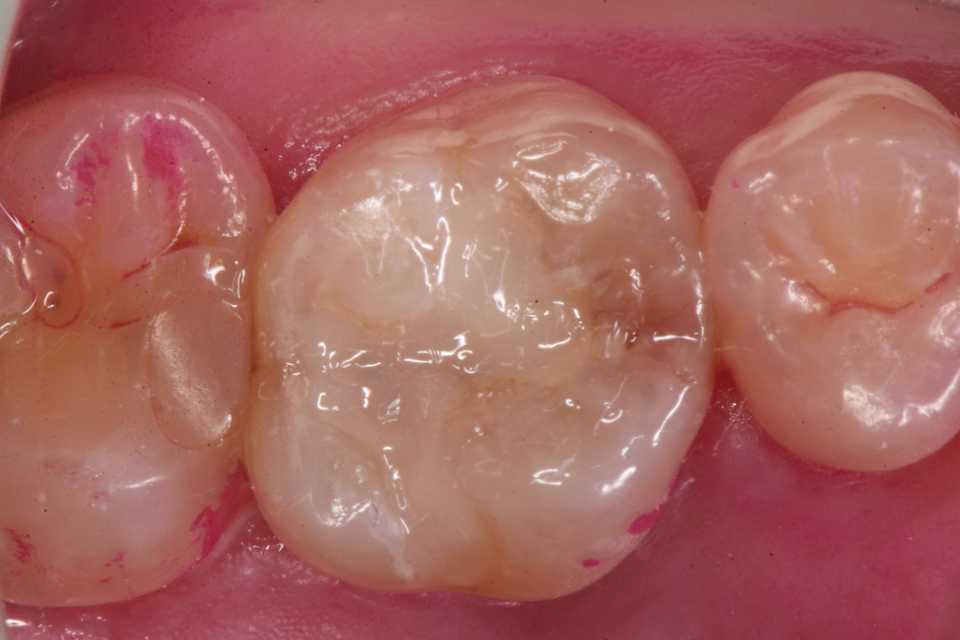

60代女性、左上5、インレー脱離ストリップス(隔壁、マトリックス)を使わないで隣接面をCRで作るというのは常識外で、一般には行われていないと思います。この技術は僕のオリジナルなのですが、慣れれば難しくはありません。フロアラブルレジンと歯質間のヌレと表面張力と重力の狭間でコントロールします。最後の隣在歯とのコンタクトポイントは接触させますが、隣接面間の弧形空隙にエキスカベーターを入れこじると剥がれます。使用材料器具や方法はフリーページにまとめています。この技術をマスターすれば、ストリップスが使えない最後臼歯のCR充填などのスーパーテクニックができるようになります。何よりその場で治療が終わりますので患者には感謝されるし、外注は要らないので経費は最小限、必要なのは自分の技量だけです。では時系列でどうぞ3MIX+α-TCP これで虫歯が治る。フロアラブルレジンを歯肉側から積み上げていく、はみ出たレジンは細い探針で残った歯面に沿わせて掬い上げるように整える。エキスカでこじるとパキッと離れるので、バリを鎌型スケーラーで整え、デンタルフロスを通す。

60代女性、左上5、インレー脱離ストリップス(隔壁、マトリックス)を使わないで隣接面をCRで作るというのは常識外で、一般には行われていないと思います。僕だけのオリジナルなのですが、慣れれば難しくはありません。フロアラブルレジンと歯質間のヌレと表面張力と重力の狭間でコントロールします。最後の隣在歯とのコンタクトポイントは接触させますが、隣接面間の弧形空隙にエキスカベーターを入れこじると剥がれます。使用材料器具や方法はフリーページにまとめています。この技術をマスターすれば、ストリップスが使えない最後臼歯のCR充填などのスーパーテクニックができるようになります。何よりその場で治療が終わりますので患者には感謝されるし、外注は要らないので経費は最小限、必要なのは自分の技量だけです。では時系列でどうぞ